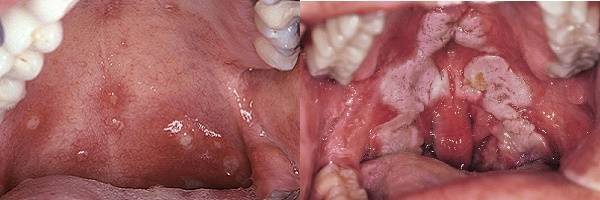

Односторонняя (атипичная) ангина или атипичный тонзиллит

Это заболевание является родственным тонзиллиту, если можно так выразиться. Главным отличием является то, что в результате генных мутаций бактерии-возбудители и вирусы поражают практически всегда (около 93% случаев) левую часть глотки. Главными провокаторами недуга, вызывающими гнойные и воспалительные процессы, являются стафилококки и стрептококки, измененные на генном уровне. Односторонняя ангина практически не передается воздушно-капельным путем, поэтому заразиться ею от другого человека невозможно.

Симптомы данного заболевания следующие:

- ярко выраженная боль в горле именно слева (без отдачи в другие зоны);

- отек и воспаление левых миндалин, их покраснение и появление на них налета, гнойничков или язв;

- выделения гнойного характера;

- общая слабость, сонливость, апатия, пропажа аппетита, реже — тошнота;

- отсутствие температуры или же она очень низкая (менее 37,3–37,5 градусов).

Атипичный тонзиллит протекает тяжелей, по сравнению с обычным, из-за чего обращение к врачу является необходимой мерой. Только специалист может точно диагностировать и правильно лечить такую болезнь. Даже у самых лучших специалистов иногда уходит до 30–40 дней на лечение данного заболевания.